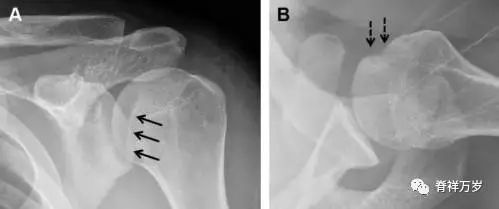

喙突骨折

喙突骨折可发生于直接*力暴**、肩关节脱位过程的肱骨头撞击、以及撕脱骨折(肱二头肌短头、喙肱肌)。

其中喙突基底部骨折最多见,常发生于直接*力暴**或肱骨头前脱位,骨折可延伸至关节盂。

而撕脱骨折多为喙突尖部的骨折。需要加拍腋位和 Stryker 位片(X 射线束以喙突为中心并头倾 10°,手臂外展,这样可以避开骨性结构的阻挡)。

有时,负重位片可发现并存的肩锁关节脱位,将有助于诊断。

图 4 喙突骨折。66 岁男性患者,猎枪射击后右肩前方疼痛。(A)内旋位前后位片投影隐约可见喙突基底部骨折(白色箭头),(B)外旋位前后位片投影结构存在重叠,(C)腋位投影时可良好显示。(D~F)喙突骨折伴 Hill-Sachs 损伤:肩关节脱位后慢性疼痛,喙突骨折块(*)向前外侧移位(双箭头),在外旋前后位(D)及腋位(E)片上均可显示,在内旋位前后位(F)片上,喙突被遮挡,但可见肱骨头 Hill-Sachs 损伤。(G、H)喙突骨折伴肩锁关节脱位,肩锁关节分离(白色双箭头),而喙锁间距正常(黑色的双箭头),应警惕喙突骨折。(I)喙突与肩峰骨化中心:对于未成年人,喙突与肩峰骨化中心可同时存在,易与骨折混淆,此时,拍对侧的 X 线片对比将有助于诊断。